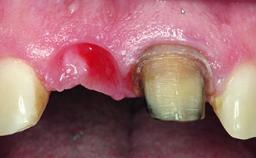

Replacement of a Failing Upper Right Central Incisor, Ridge Preservation and Late Placement of a NC Bone Level Implant

A 30-year-old patient presented at our clinic with a chief complaint of pain in her endodontically treated right maxillary central incisor (tooth 11) with a post-and-core and a fixed single crown. She had a very high lip line, a medium to thin soft-tissue phenotype, and a medium scalloped gingival contour. She also had high esthetic expectations because of her young age and beautiful smile. However, her expectations were realistic and she understood the risks of the treatment. At the initial clinical examination there was a slight mobility of tooth 11; no fistula was observed. The patient also had a single crown on the adjacent tooth 21. Both restorations were old and esthetically deficient. A digital periapical radiograph showed a very small periapical radiolucency, a thick intraradicular post, and no separation between root fragments.